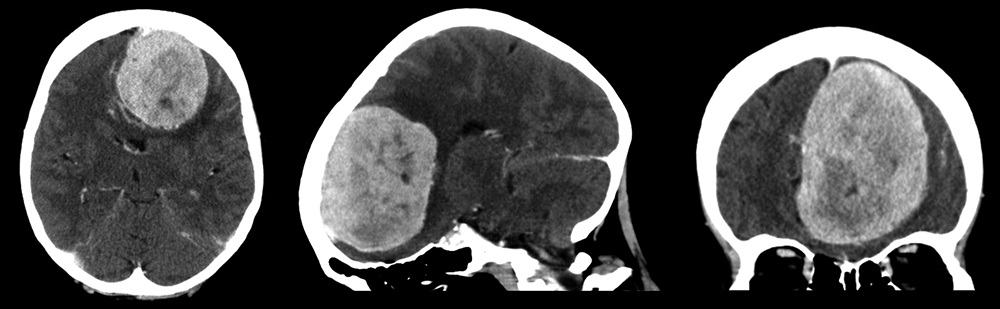

En kvinne i slutten av 70-årene ble innlagt på medisinsk avdeling grunnet manglende evne til egenomsorg. Hun fremsto som apatisk, mimikkfattig og svært ordknapp, men somatisk og nevrologisk undersøkelse viste ellers normale funn. Pasienten hadde ikke hatt urgeinkontinens eller ukritisk atferd. Pårørende bemerket at hun var blitt økende glemsk i løpet av det siste året. Demensutredning var startet, men det var ennå ikke gjort bildediagnostikk. Ved innleggelsen ble det derfor gjort en CT-undersøkelse av hjernen med kontrast (bildene). Denne viste en 5 × 6 × 8 cm stor velavgrenset kontrastladende tumor med midtlinjeforskyvning og omkringliggende ødem i venstre frontallapp, best forenlig med et stort parasagittalt meningeom. Videre MR-undersøkelser forsterket denne mistanken.